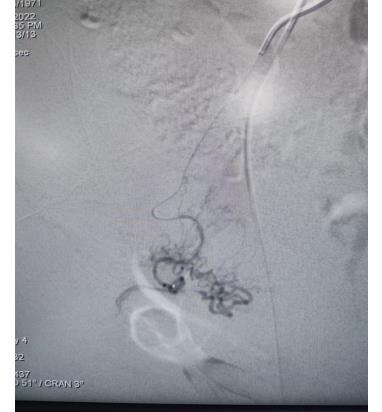

子宫动脉栓塞术属于血管介入性治疗,方法是于股动脉穿刺进针插入导管,在X射线造影下定位进入两侧子宫动脉,注入栓塞剂完全栓塞子宫动脉,从而达到止血或让子宫肌瘤和病灶缺血坏死的目的;2022年12月6日,在崔旭辉主任、孟庆槐副主任医师、马力主治医师等我院介入团队协作下,成功为患者进行了双侧子宫动脉栓塞术,术后患者子宫异常出血停止,效果立竿见影,患者病情恢复良好。

左侧子宫动脉栓塞前后对照

右侧子宫动脉栓塞前后对照